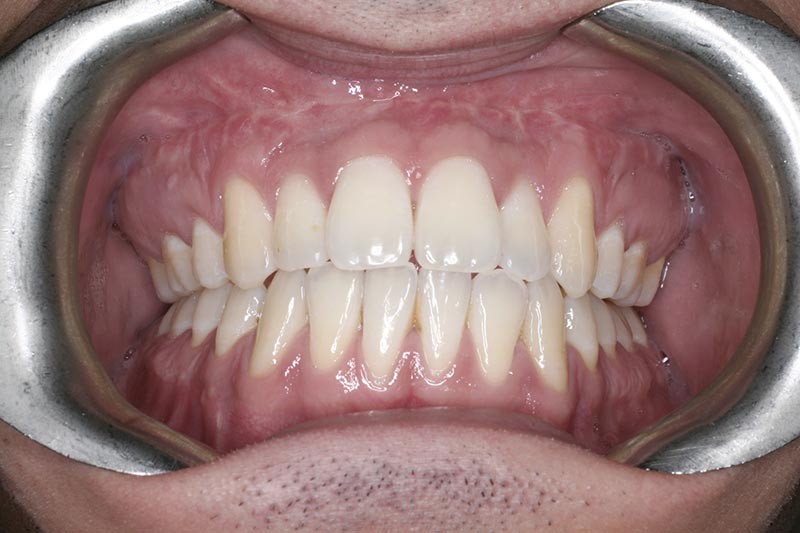

Les résultats esthétiques et occlusaux satisfont amplement le patient qui revient pour un contrôle à long terme 10 ans après l’intervention montrant la stabilité des résultats.